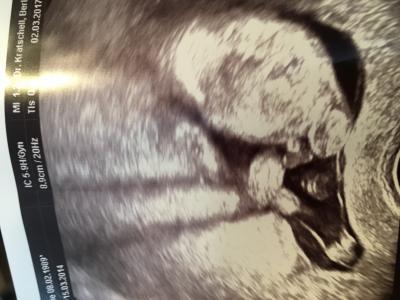

Hey ihr lieben :) war heute bei 14+4 beim Arzt und er meinte er denkt es wird ein Junge. Er hat mir extra das Bild von unten ausgedruckt. Man sehe da die Hoden. Aber ist das nicht zu früh? Erkennt ihr was auf dem Bild? Versuche mal ein Bild anzuhängen. Lg P.s das Bild ist, warum auch immer, nicht so wie ich es fotografiert habe (also verdreht). Hoffe ihr erkennt tzd was ich meine ^^

Oh ja, das sieht man ja ganz deutlich! Bin gerade mit Jungs Nr. 3&4 schwanger und so sah das jedes Mal aus. Die Jungs sind da sehr zeigefreudig. Bei uns hieß es beim Schallen immer: Das Gesicht ist leider verdeckt, aber das Geschlecht könnte ich Ihnen nochmal ganz deutlich zeigen. (Dankendes Abwinken. ) LG Tine

Ich mache nachher noch mal ein US, wo man alles sieht, auch das Datum! Damit du siehst das ich es nicht nötig habe hier fremde Bilder reinzustellen ;) und ich versuche es so reinzustellen; das es richtig rum ist. Man sieht den Bauch, die Beine und am Bauch halt laut Arzt Hoden und Penis.

Den anderen auf jeden Fall schon mal Danke. Bin halt noch immer skeptisch, weil ich sehr unsicher bin. Eher denke es ist die Nabelschnur. Habe einen 3jährigen Sohn, bei dem es anders aussah.

Die Nabelschnur ist es nicht. Sie wäre weiter oben.

Hier eindeutig Penis und Hoden